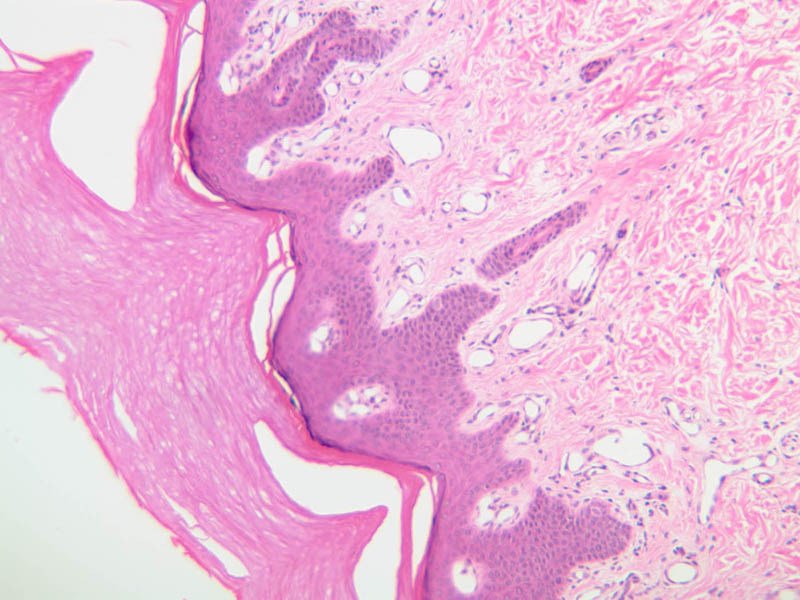

For general orientation, note that skin has two components, epidermis (a stratified squamous epithelium) and dermis (a connective tissue layer beneath the epidermis). Epidermal ridges project into the dermis, enclosing between them the highly vascular dermal papillae. Beneath the dermis lies the subcutaneous tissue, a loose layer of connective tissue, fat, blood vessels, and nerves. The skin appendages are situated partially in the dermis and partially in the subcutaneous layer. The skin consists primarily of two cell types; a keratin-producing epithelial cell (keratinocytes) and a pigment cell of neural crest origin (melanocyte). Langerhans cells are also present. These are believed to be antigen presenting cells of the epidermis. The keratinocytes exhibit morphological and functional stratification from base to surface of the epithelium and thus provide a basis for distinguishing several layers of the epidermis.

Examine slide A-50 (fingertip, H&E [2.5x, 10x-labeled, 20x, 40x-labeled] [20x, 40x] [10x, 20x, 40x] [20x, 20x, 40x]), and study the morphology of five layers of thick skin. The deepest part of the epidermis comprises the stratum basale which provides the cells required for continual renewal of the epidermis. This stratum is composed of a single layer of columnar or cuboidal epithelial cells attached to the basement membrane.

Superficial to the stratum basale is a multi-cellular layer known as the stratum spinosum, consisting of polyhedral cells that have a "prickly" or spiny appearance (A-50, langerhans cells [10x, 20x-labeled, 40x-labeled] [40x, 40x-labeled, 40x, 40x-labeled]; A- 48, abdominal skin, H&E [10x, 20x, 40x] [40x, 40x, 40x, 40x]). The spiny cells are separated by intercellular spaces that are bridged at numerous points by cytoplasmic processes, which in turn are bound together by desmosomes. The cytoplasmic processes projecting on all sides from the cells give them the spiny appearance to which the name refers. These are best seen under high power. Langerhans cells can also be found in this layer.

Superficial to the stratum spinosum is a layer of flattened cells with coarse, deeply-stained cytoplasmic granules, the stratum granulosum (slide A-50 [40x] [40x, 40x] [40x-labeled, 40x, 40x]). These are keratohyalin granules and evidently represent a stage in the keratinization of the epidermal cells. Note that the nuclei of the more superficial granular cells appear dense and pyknotic, foreshadowing their disintegration and the resultant death of the cells.

The stratum lucidum is often considered to be a subdivision of the stratum corneum. This layer is evident only in thick (glaborous) skin. It appears as a clear band beneath the stratum corneum. Cells of the stratum lucidum are well advanced in the process of keratinization. Consequently, the nucleus and many of the cytoplasmic organelles become disrupted and disappear as the cells become filled with the intracellular protein keratin. In many specimens, there is a separation artifact at this point. The outermost layer of the epidermis is called the stratum corneum and is composed of fully cornified (keratinized) remnants of epithelial cells ([40x]). It has a basketweave appearance. The close union of the resulting scales with each other, and their content of insoluble protein and extracellular lipids, provides a barrier to diffusion between the body and its external environment.